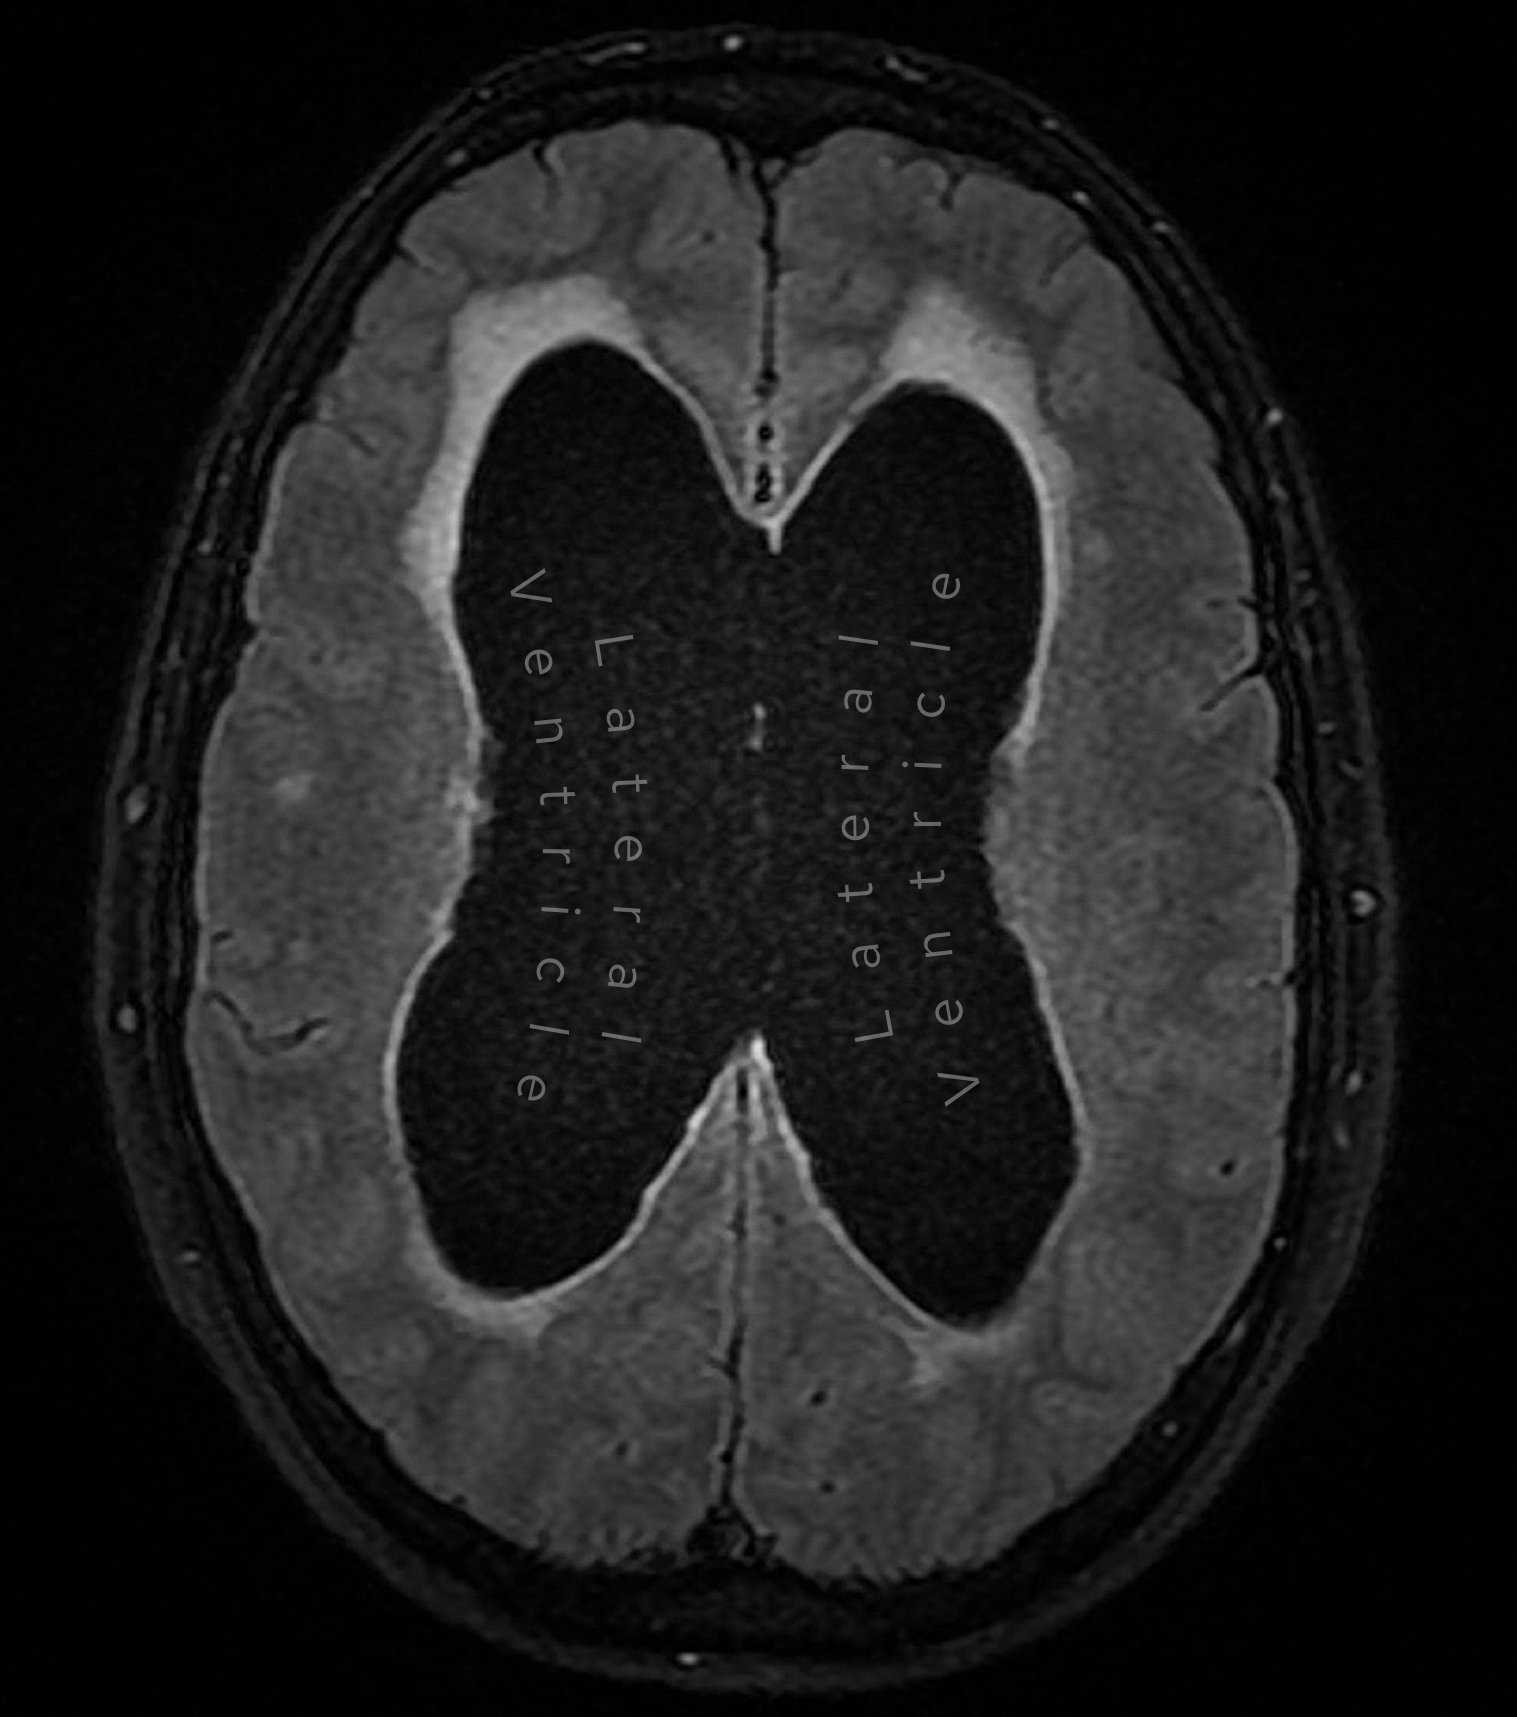

Case 5

A female in her 50s presents with gait disturbance. Here are two images from a MRI head (FLAIR sequence). What is the most likely diagnosis?

Choose from one of the following options: